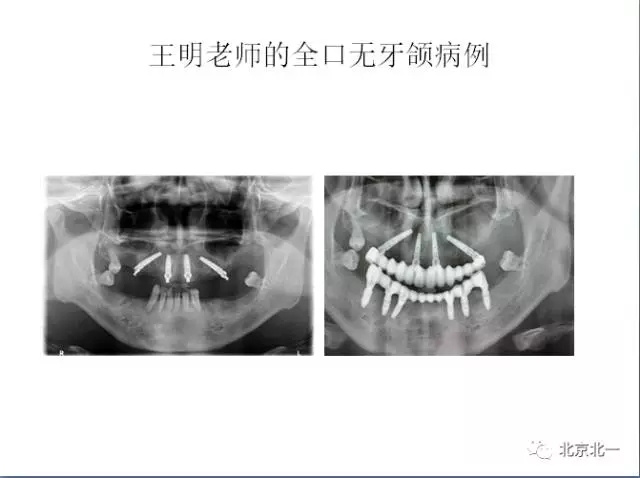

王明

北一種植聯(lián)盟首席專家;

擅長:種植外科,尤其專長復雜牙種植,自體骨移植同期種植,上頜竇底內(nèi)外提升同期種植技術,美學區(qū)種植技術,即刻種植外科與即刻負重技術,軟組織成形外科種植技術及全口無牙頜ALL-ON-FOUR技術,種植并發(fā)癥和種植急癥處置等手術治療,從事口腔頜面外科,正頜外科、頜面部整形、微創(chuàng)拔牙,笑氣無痛舒適種植十余年。

畢業(yè)于中山大學光華口腔醫(yī)學院,擅長各型牙列缺損缺失的種植義齒修復。

2014年榮獲全國第三屆BITC 口腔種植病例大獎賽優(yōu)秀獎。